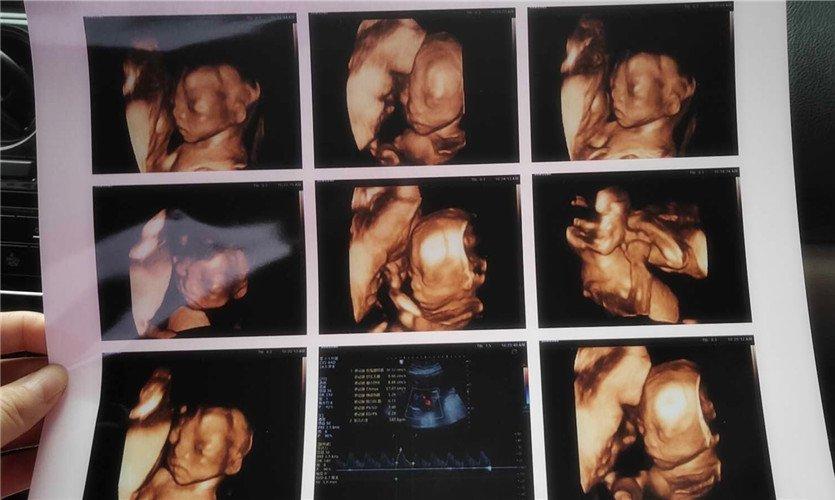

四維彩超是一種先進(jìn)的醫(yī)學(xué)影像技術(shù),通過(guò)實(shí)時(shí)觀察胎兒在母體內(nèi)的活動(dòng)情況,為醫(yī)生提供了豐富的診斷信息,在四維彩超下,我們可以清晰地觀察到胎兒的蛋蛋(睪丸)的形態(tài)、位置和大小等特征,胎兒蛋蛋是男性生殖系統(tǒng)的重要組成部分,對(duì)于胎兒的生長(zhǎng)發(fā)育具有重要意義。

在四維彩超下,胎兒蛋蛋呈現(xiàn)出特定的形態(tài)和外觀,通常情況下,胎兒蛋蛋呈現(xiàn)出圓形或橢圓形,表面光滑,內(nèi)部回聲均勻,隨著胎兒的發(fā)育,蛋蛋會(huì)逐漸增大,并呈現(xiàn)出明顯的性別特征,醫(yī)生可以通過(guò)四維彩超技術(shù),對(duì)胎兒蛋蛋的大小、形態(tài)和位置進(jìn)行評(píng)估,以判斷胎兒生殖系統(tǒng)的健康狀況。

胎兒蛋蛋的發(fā)育是一個(gè)復(fù)雜的過(guò)程,受到多種因素的影響,在胎兒發(fā)育的早期階段,蛋蛋位于腹腔內(nèi),隨著胎兒的生長(zhǎng)發(fā)育,蛋蛋逐漸下降至陰囊,這個(gè)過(guò)程受到激素、遺傳和環(huán)境等多種因素的影響,在四維彩超的觀測(cè)下,我們可以實(shí)時(shí)了解胎兒蛋蛋的發(fā)育過(guò)程,及時(shí)發(fā)現(xiàn)異常情況并采取相應(yīng)的治療措施。